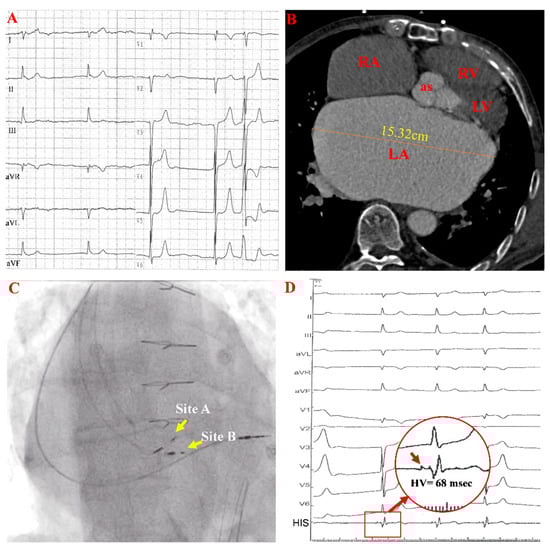

A 70-year-old man presented with exertional dyspnea and recurrent presyncope for two months and was admitted to our center. He had rheumatic heart disease and chronic AF for nearly 30 years without any sinus rhythm documented on multiple electrocardiograms (ECGs). Six years ago, he underwent mitral valve replacement (E100-29M-00, Epic, St. Jude Medical Inc., St. Paul, MN, USA) and tricuspid valvuloplasty for severe rheumatic mitral stenosis and tricuspid insufficiency. The admission ECG showed AF with a slow ventricular rate (Figure 1A). The 24 h ambulatory ECG demonstrated persistent AF with a slow ventricular rate of 46 beats per minute (BPM), and paroxysmal complete atrioventricular block (AVB) with a junctional escape rhythm. Coronary computed tomography angiography (CTA) revealed a severely enlarged left atrium (Figure 1B). A permanent pacemaker was indicated for symptomatic bradycardia. Although the left ventricular ejection fraction (LVEF) was preserved, the actual LVEF might have been overestimated due to mitral regurgitation. Moreover, considering that the patient was expected to have a ventricular pacing requirement most of the time and his apparent biatrial enlargement, we tried His-bundle pacing (HBP) to obtain better cardiac mechanical synchrony.

During implantation, HBP (Figure 1C, site A) using the Select Secure lead (model 3830, Medtronic Inc., Minneapolis, MN, USA) was attempted with right ventricular pacing (RVP) as a backup (Figure 1C). A clear His-bundle potential was observed, and the His-ventricular (HV) interval was 68 ms at site A (Figure 1D).

Figure 1. Images and ECGs before HBP. (A,B) show a preprocedural ECG and large left atrium in cardiac CTA. (C,D) are fluoroscopic AP views and electrograms with prolonged HV intervals during the procedure. In panel (D), the red arrow in the red circle indicates the HB potential. AP: anteroposterior projection; RA: right atrium; LA: left atrium; RV: right ventricle; LV: left ventricle; as: aortic sinus.